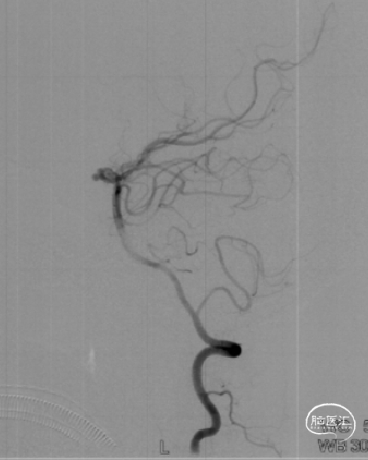

术后6个月随访:

复查脑血管造影示:右侧大脑中动脉支架置入术后,支架位置良好,管腔内血流通畅,未见明显狭窄。

术后2年随访:

复查脑血管造影示:右侧大脑中动脉支架置入术后恢复良好,支架位置精确无误,其管腔血流通畅,未见任何明显狭窄,手术效果满意。

2023-02-06 6M-FU (正位)

2023-02-06 6M-FU (侧位)

2024-08-07 2Y-FU (正位)

2024-08-07 2Y-FU (侧位)